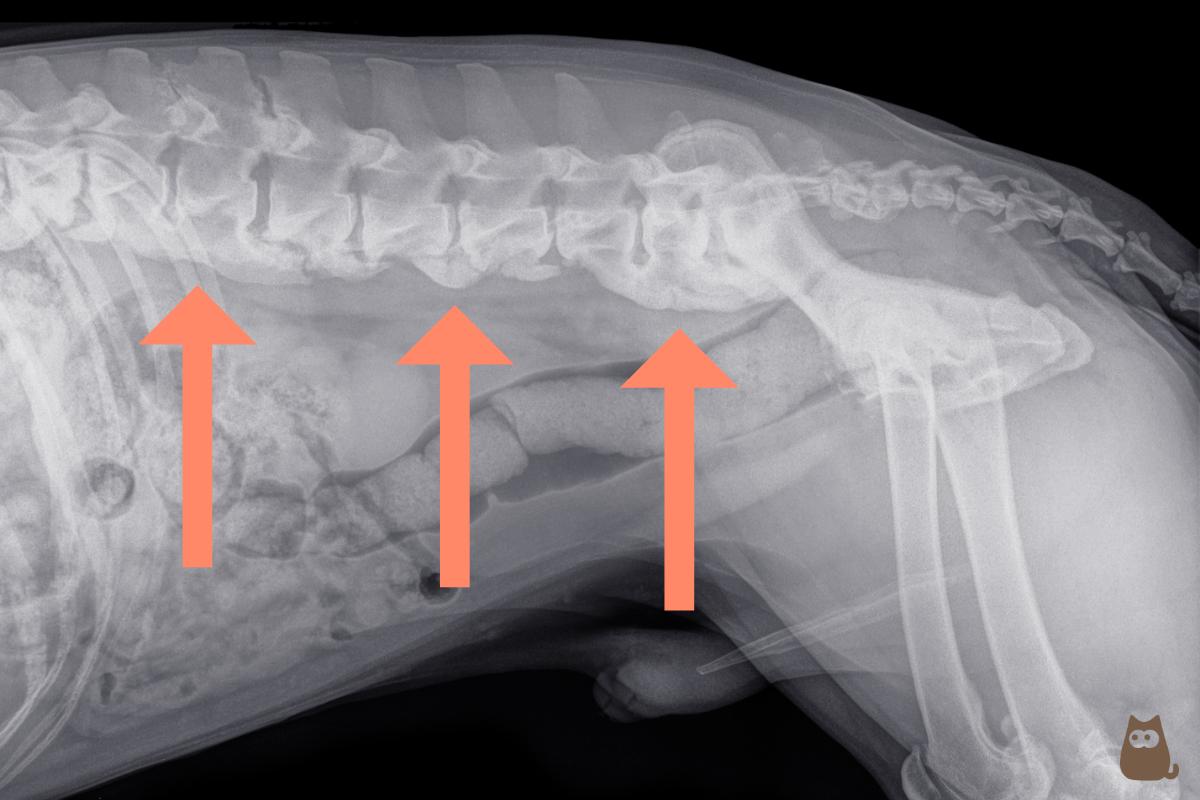

En la exploración radiográfica, la espondilosis se observa en forma de protrusiones (osteofitos) del borde inferior de las vértebras hacia los extremos anterior y posterior de las vértebras adyacentes. A medida que progresa, adquiere un aspecto en forma de gancho que comúnmente recibe el nombre de “pico de loro”. En los casos más avanzados, se llega a formar un puente que une los cuerpos de las vértebras a nivel ventral. Cuando únicamente se observa un osteofito aislado en una vértebra, se suele hablar de espondiloartrosis canina.